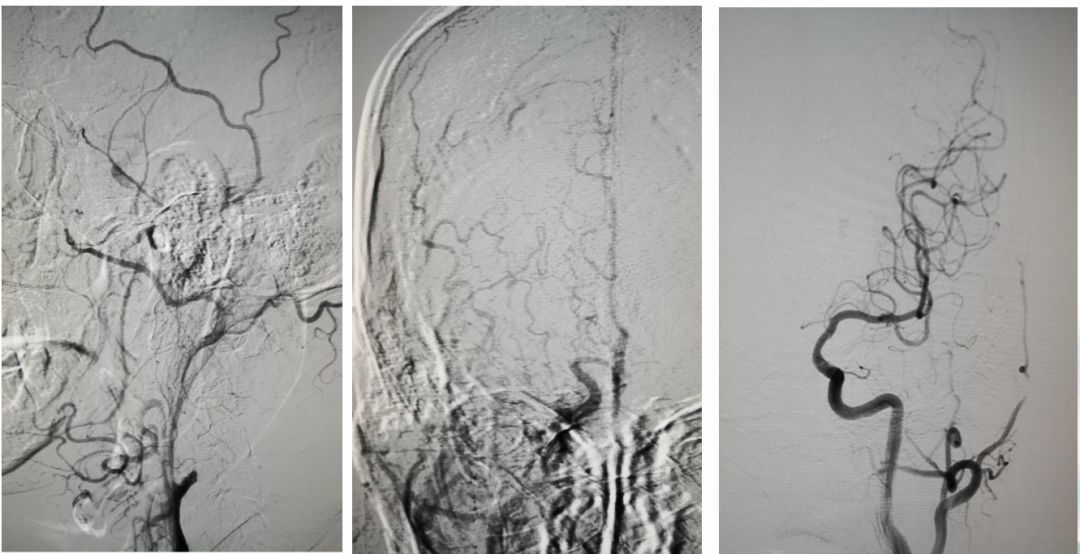

术前造影:

串联病变

ASITN/SIR 2级

球囊扩张

微导管在血栓远端造影

支架到位释放透视图+造影图

异常早显静脉

取出栓子

术后正侧位造影图片